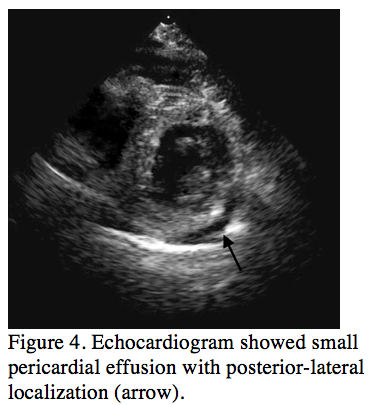

Figure 3. Repeated coronary angiography showed left coronary artery stent was patent without contrast extravasation (click thumbnail to view larger image).

Thirty-six hours after the procedure, the patient complained of severe chest pain and mild dyspnea. She developed a low-grade fever (38°C) and a pericardial friction rub was noted on auscultation. Laboratory data revealed leucocytosis (14 x 109/L) and an elevated C-reactive protein level (40.6 mg/dL), although cardiac biomarkers remained within normal limits (troponin-I of 0 ng/mL, CK of 24 U/L, CK-MB of 3 U/L). Furthermore, her ECG showed ST-elevation in inferior leads, ST-depressions in V1-2 and elevations in V4-V6 (Figure 1B), suggesting acute ST-elevation myocardial infarction of the inferior-lateral walls with extension to the posterior wall. Emergent coronary angiography revealed no evidence of coronary artery occlusion and no evidence of contrast extravasation in the distal D2 (Figure 3).